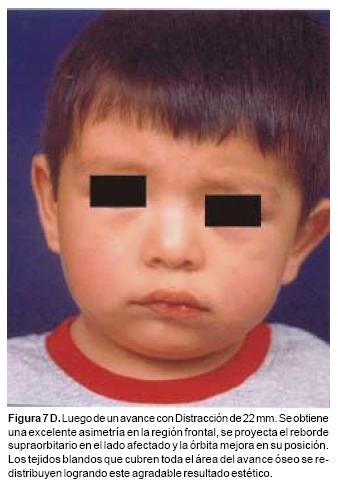

También los controles radiológicos durante el proceso de distracción mostraron que no se produjo la creación de espacios muertos intracraneanos durante los avances. En todos los pacientes con sinostosis bicoronal el avance frontoorbitario produjo excelentes resultados estéticos dando una nueva forma a la región frontal y proyectando mejor el reborde supraorbitario. En los niños con enfermedad de Crouzon y síndrome de Apert, se corrigió en forma muy satisfactoria el exorbitismo al resolver las graves exposiciones corneales (Figuras 5 A, B, C, D, E, F, G, H), en los que se utilizó el avance simultáneo del tercio medio, este cambio óseo corrigió muy satisfactoriamente la retrusión del mismo, ampliando la vía aérea y resolviendo en muchos casos grandes problemas ventilatorios durante el sueño (Figuras 6 A, B, C, D, E, F). Los pacientes con plagiocefalia corrigieron significativamente la deformidad frontoorbitaria y los tejidos blandos suprayacentes se adaptaron a la nueva estructura ósea. La clásica órbita de arlequín de estos niños producida por la sinostosis del frontal con el esfenoides, inmediatamente se ve corregida en su forma y su configuración se hace muy similar con la órbita contralateral (Figura 7)(Fig. 7a, 7b, 7c, 7d, 7e, 7f, 7g) (Cuadro II).